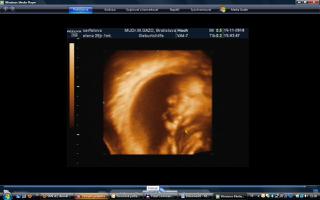

vcera som mala poradnu a teda dopadla pre mna dost prekvapujucu. mala je uz mesiac otocena dolu hlavickou a tlaci sa a tlaci. krcok sa mi zacal skracovat, ale zatial sa neotvara. a aby toho nebolo malo, tak mam aj iritabilnu maternicu. buducu nedelu idem do nemocnice na premeranie krcka a uvidi sa, co bude. aspon, ze ju uvidime 3D potvorku malu nedockavu 🙂 do mesiaca mi zrejme bude treba zaviest pesar.. tooolko radosti naraz a to som povodne vobec nemala mat poradnu, kedze som povodne dosla len s babkou na kontrolu..tak vysetrila aj mna.

caute baby. uz som tu dlho nebola. nejako nestiham. My sme uz boli na tiez na 3D a zase mala mala rucicky pred tvarickou ale daco bolo aj vidno. takze sme zistili, ze sa podoba na muza, teda aspon ten nos usta. Ma skoro 500 g takze je asi o tyzden posunuta neskor.Ak sa mi bude dat tak pridam dake fotky z toho dvd co som vybrala. Inac ja som kupovala tehotenske pancuchy v Brendone v Ba za 4 Eura. teda tenke ale mali tam aj hrubsie a tie stali 15 eur. Ja tiez rozmyslam rodit v ruzinove ale asi skor na Kramaroch. to mam blizsie domov. Ja si doplacam od marca dobrovolne nemocenske poistenie k povinnemu do maximalneho vymeriavaceho zakladu, aby som mala maximalnu matersku. Takze snad s tou materskou sa to bude dat ale horsie to bude s tym rodicovskym prispevkom.